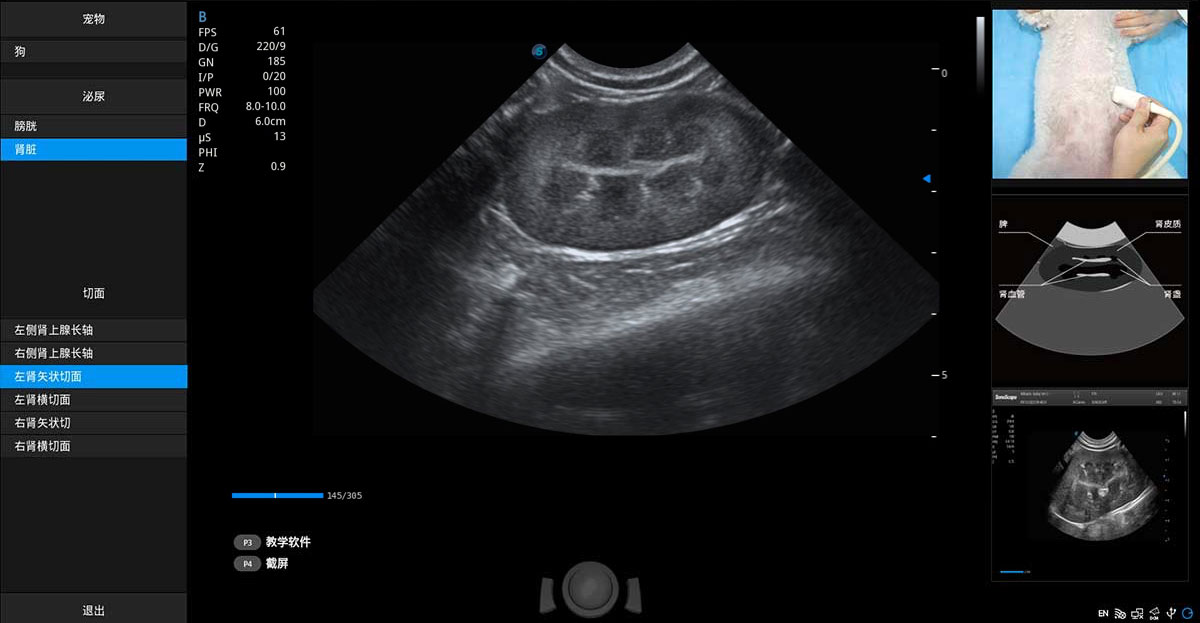

提供解剖示意圖、標(biāo)準(zhǔn)超聲圖像、掃查手法圖和操作者實(shí)時檢查圖像,指導(dǎo)操作者進(jìn)行標(biāo)準(zhǔn)切面的正確掃查。

ProPet 70專為動物醫(yī)生設(shè)計,對不同的動物體型和生理結(jié)構(gòu)作出了針對性的優(yōu)化。通過動物影像專用軟件,可滿足個性化的應(yīng)用需求,幫助動物醫(yī)生獲得更精確的診斷數(shù)據(jù)。

ProPet 70 進(jìn)一步提升了微米成像算法,更加注重對基礎(chǔ)原始圖像的還原和保留,在有效減少斑點(diǎn)噪聲、增強(qiáng)組織邊界顯示的同時,避免過度優(yōu)化丟失真實(shí)的解剖信息。